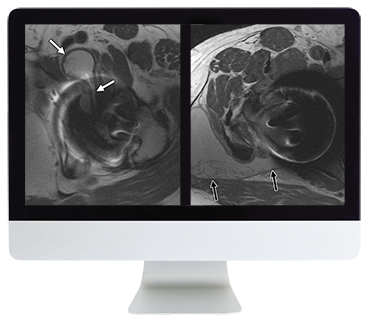

ARRS Controversies In Hip And Pelvis Imaging 2016 (CME VIDEOS) This Online Course provides established principles and new concepts regarding pathology of the hip and pelvis, with an emphasis on MRI. Lectures cover a number of clinically important topics, including pitfalls and postoperative findings essential to the practicing radiologist.

- identify acetabular labral tear on MRI with improved confidence